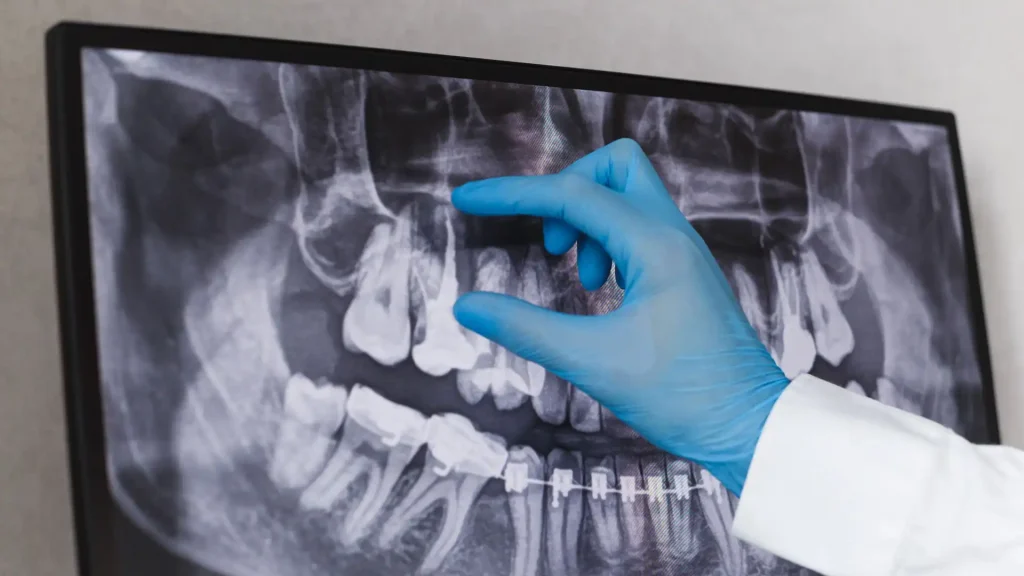

Brezilya’daki araştırmacılar, diş röntgenlerine dayanarak bir bireyin cinsiyetini doğru bir şekilde belirleyebilen bir yapay zeka sistemi geliştirerek adli diş hekimliğinde önemli bir ilerleme kaydetti. Erişilen önemli bulgular, yapay zekanın, diş röntgenlerinden cinsiyet belirlemede yüksek doğruluk elde ettiğini ortaya koyuyor. 200.000’den fazla panoramik radyografi üzerinde eğitilen makine öğrenimi sistemi, yüksek çözünürlüklü görüntüler kullanıldığında 16 yaşın üzerindeki bireyler için cinsiyet tahmininde %96 gibi etkileyici bir doğruluk oranı gösterdi. Çalışmada iki tür derin öğrenme algoritması kullanılmıştır. Her ikisi de diş röntgeni görüntülerinden özellik hiyerarşilerini öğrenmek için optimize edilmiş bir konvolüsyonel sinir ağı ve bir adet artık ağdır. Görüntü çözünürlüğü sistemin doğruluğunda çok önemli bir rol oynamış, daha yüksek çözünürlük daha iyi performansa yol açmıştır. Yaş da doğruluğu etkilemiş, yapay zeka 20 ila 50 yaş arasındaki hastalar için en iyi performansı gösterirken (%97’nin üzerinde doğruluk), 70 yaşın üzerindekiler için biraz daha düşük performans sergilemiştir (%95’in hemen altında). Daha genç bireyler için, sistemin doğruluğu 6 ila 16 yaş arasındakiler için %87’ye ve altı yaşından küçük çocuklar için %74’e kadar düştü.

Bu araç, adli diş hekimliği için daha geniş çıkarımlar sağlamıştır. Yapay zeka destekli araç, özellikle toplu kazalar veya çeşitli çürüme aşamalarındaki cesetleri içeren vakalar gibi zorlu durumlarda, diş kalıntılarına dayanarak bireylerin kimliklerinin belirlenmesinde adli tıp uzmanlarına yardımcı olma potansiyeline sahiptir. Geleneksel adli tıp yöntemleri genellikle cinsiyeti belirlemek için kemiklerin ve yapılarının analiz edilmesine dayanır, ancak bazı durumlarda inceleme için yalnızca çene ve dişler mevcut olabilir. Bu çalışma, dişler, çeneler ve çevre yapılar da dahil olmak üzere tüm ağzın kapsamlı bir görüntüsünü yakalayan panoramik radyografilerden değerli bilgilerin çıkarılmasında yapay zekanın etkinliğini göstermektedir. Yapay zeka, cinsiyet belirleme sürecini otomatikleştirerek insan hatalarını azaltmaya yardımcı olabilir ve daha hızlı tanımlama sağlayarak potansiyel olarak adli diş hekimliği uygulamalarında devrim oluşturabilir. Çalışma, cinsiyet belirleme için umut verici bir yapay zeka aracı sunarken, araştırmada kullanılan görüntülerin yaşayan bireylerden geldiğini ve sistemin etkinliğinin ileri çürüme aşamalarındaki insan kalıntılarına uygulandığında farklılık gösterebileceğini belirtmek önemlidir. Diş röntgenlerinden cinsiyetin belirlenmesinde yapay zekanın başarılı bir şekilde uygulanması, adli diş hekimliği için yeni olanaklar sunmakta ve yapay zekanın çeşitli alanlarda artan rolünü vurgulamaktadır. Araştırmalar devam ettikçe, bu tür yapay zeka güdümlü araçların daha fazla iyileştirilmesi ve doğrulanması, adli tıp uygulamalarında yaygın olarak benimsenmelerine yol açabilir ve sonuçta kimlik belirleme süreçlerinin verimliliğini ve doğruluğunu artırabilir.